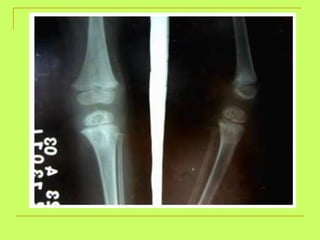

Age from lower limb examination 1) Lesser trochanter  (16y )-----Greater trochanter  (17y)  ------ Head of the femur  (18y). 2) Lower end of the femur + shaft  (21y). 3) Upper end of the tibia +shaft  (21y). 4) Lower end of the tibia +shaft  (18 y).   By foot examination ossific center appears at calcanium at  6 years  and union of epiphysis at the calcanium at  14 years  ,so examining only this bone gives us a range of 8 years

What is the age ? >18 years (united head of femur)

What is the age? above18ys

Age from lowerlimb examination 1) Lesser trochanter (16y )-----Greater trochanter (17y) ------ Head of the femur (18y). 2) Lower end of the femur + shaft (21y). 3) Upper end of the tibia +shaft (21y). 4) Lower end of the tibia +shaft (18 y). By foot examination ossific center appears at calcanium at 6 years and union of epiphysis at the calcanium at 14 years ,so examining only this bone gives us a range of 8 years

What is theage ? >18 years (united head of femur)

What is theage? above18ys